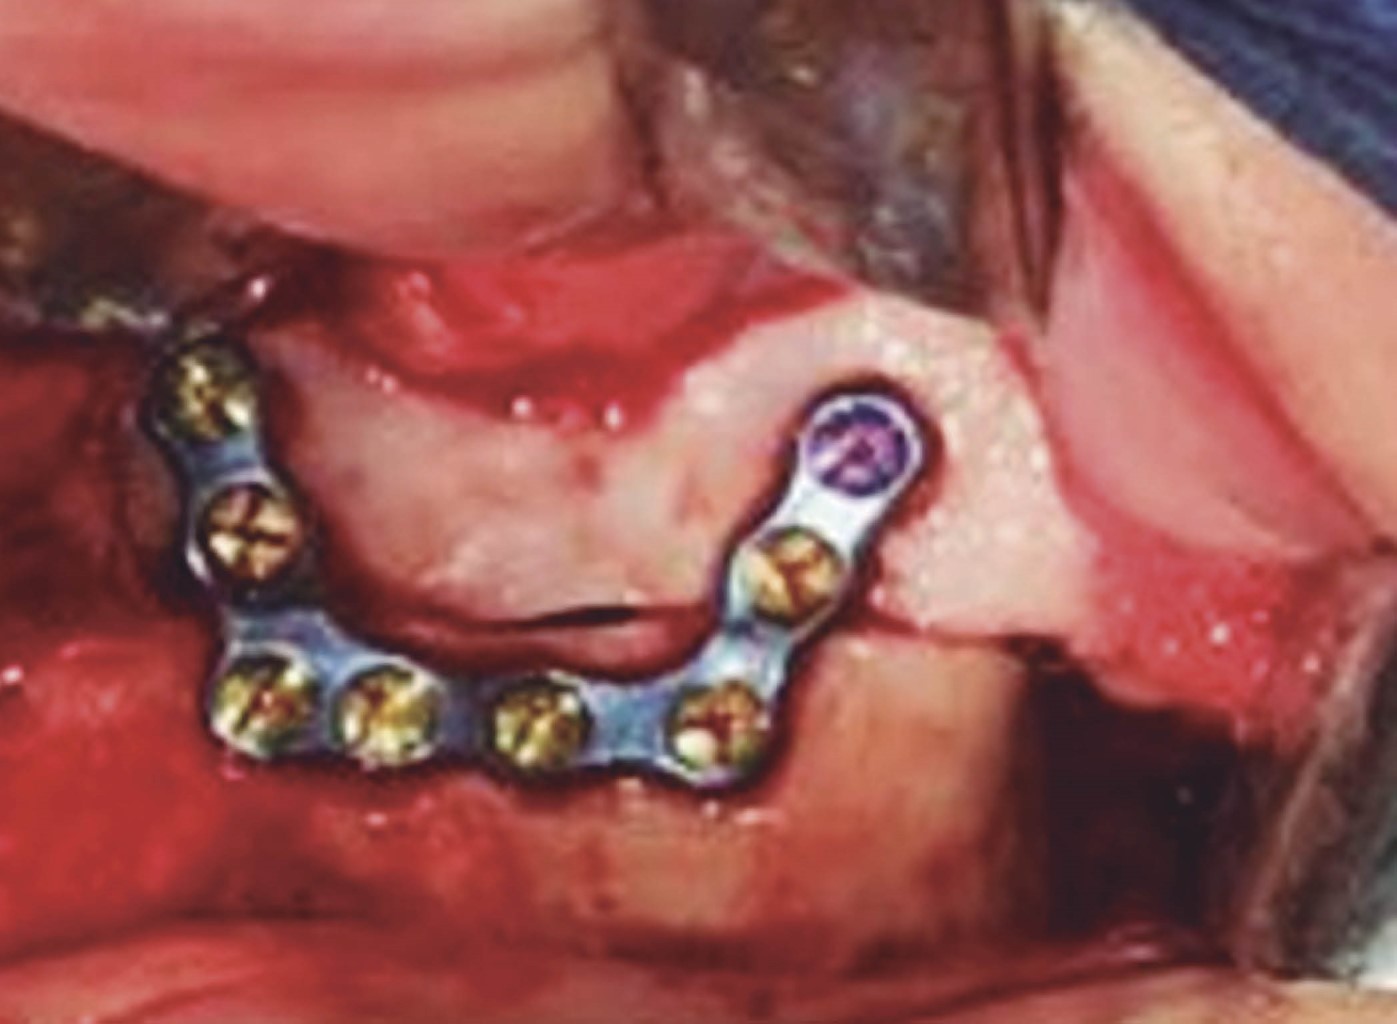

Introduction: currently, computer-aided planning of orthognathic surgery helps us obtain better results, avoiding errors that could occur with conventional orthognathic surgery planning. With virtual planning of orthognathic surgery, we obtain surgical guides that help us stabilize the maxillary segments during surgery to avoid recurrences. Currently, the use of cutting guides and customized plates in Le Fort I osteotomy eliminates the need for occlusal surgical guides, minimizing surgical time, making the surgery more agile, and improving results. Clinical case: a 20-year-old female patient was diagnosed with maxillary vertical excess and anterior open bite. Surgery was performed using virtual surgery to plan a 4 mm Le Fort I impaction osteotomy, using custom-made titanium plates and cutting guides during the procedure. Results: the advantages of using this management protocol in orthognathic surgery are: reducing pre- and intraoperative work time, minimizing errors in surgical movements, developing simpler and more precise surgical procedures, avoiding injuries to the anatomical structures involved, transferring the results of the virtual simulation in the manufacture of cutting templates to the operating room, obtaining highly satisfactory results, carrying out and establishing an optimization protocol and finally obtaining a database of surgical patients. Conclusions: it is a versatile technique, with a minimum degree of difficulty and easy to perform.

Figure 2